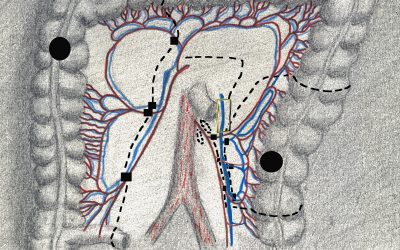

Opportuni criteri per definire l’estensione dell’escissione mesorettale consentono di scegliere appropriatamente tra sezione “alta” e sezione “bassa” dell’arteria mesenterica inferiore nelle resezioni colo-rettali per adenocarcinoma del retto

di Enrico Ganz In questo articolo analizzo dapprima le conoscenze relative al livello di sezione arteriosa mesenterica nelle resezioni colo-rettali per adenocarcinoma del retto. Pervengo alla conclusione che la principale finalità di una sezione mesenterica...